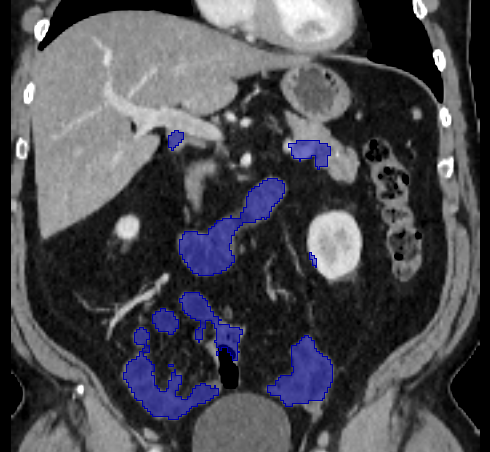

Over the years, there have been attempts to develop automatic methods for small bowel segmentation, especially using deep learning. The small bowel was included in segmenting multiple organs-at-risk for radiotherapy treatment planning of affected tissues, such as pancreatic and cervical cancers, in CT scans [8, 9, 13]. Although the results obtained for the small bowel are reasonable, some of their data included only the part of the small bowel that is closest to the target area, which needed to be dose-evaluated [8, 9]. In [13], the rough bowel location was detected instead of performing pixel-accurate small bowel segmentation. There have been only a few previous works dedicated solely to automatic small bowel segmentation [12, 14, 21]. While the specific anatomic relationship between the mesenteric vasculature and the small bowel is used to guide the small bowel segmentation in [21], a cylindrical shape constraint is applied during training of the small bowel segmenter in [14]. Although each of the works showed reasonable performance for particular datasets, their generalizability across different datasets was not evaluated. A CT scan is acquired using a specific imaging protocol depending on the purpose of the investigation, which includes the use of different contrast media and scan timing. Thus, the appearance of the small bowel may be different across datasets as exemplified in Figure 1. It is observed in our experiment that, when trained on one dataset, the model does not generalize well to another dataset due to the domain shift (section 3).

In this paper, we present a novel unsupervised domain adaptation method for small bowel segmentation, which is based on feature disentanglement. Although the absolute intensity values in CT scans (Hounsfield units) carry important information on specific substances of the human body, thus could provide a clue of being specific tissues and organs, they may be variable according to the imaging protocol. Figure 1 shows example CT scans that were acquired with and without oral contrast administration. The absolute intensity values are no longer a strong clue for the small bowel when we train and test across the datasets. Non-intensity features like texture and shape may be more useful. For example, local textures of the valvulae conniventes, which are circular folds on the inner surface of the small bowel, are more recurrent across the datasets.

3.2 Qualitative Evaluation

Figure 3 shows example segmentation results in 3D. The result corresponding to ‘feat. & out. level DA’ in Table 1 is compared to ours. We note that the only difference between them is whether the feature disentanglement is involved for the domain adaptation, thus could show its effectiveness. Fewer errors are observed for the proposed method. We believe this is because the proposed method explicitly concentrates on the features more transferable across the datasets, the non-intensity features in this work, by disentangling those features and applying adversarial learning directly to them during the adaptation process. Example reconstruction results from the auto-encoding architecture as well as segmentation results in coronal view can be found in supplementary material.